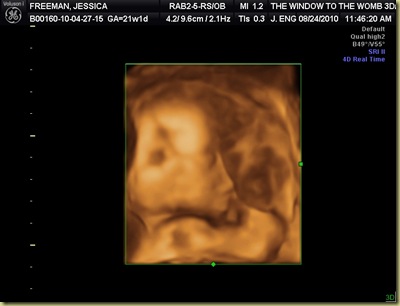

Today’s appointment went fairly well. Baby looks super healthy and guess what we are having?????!!!!!!!! Haha – fooled ya – we won’t know until Birth Day =) But sweet little one was constantly squished up against the placenta today and would not show his/her face – this is the best picture the Dr. could get – can you see the face and the little arm above?

Below is a photo of the spine and little leg in the bottom right. Super crazy looking.